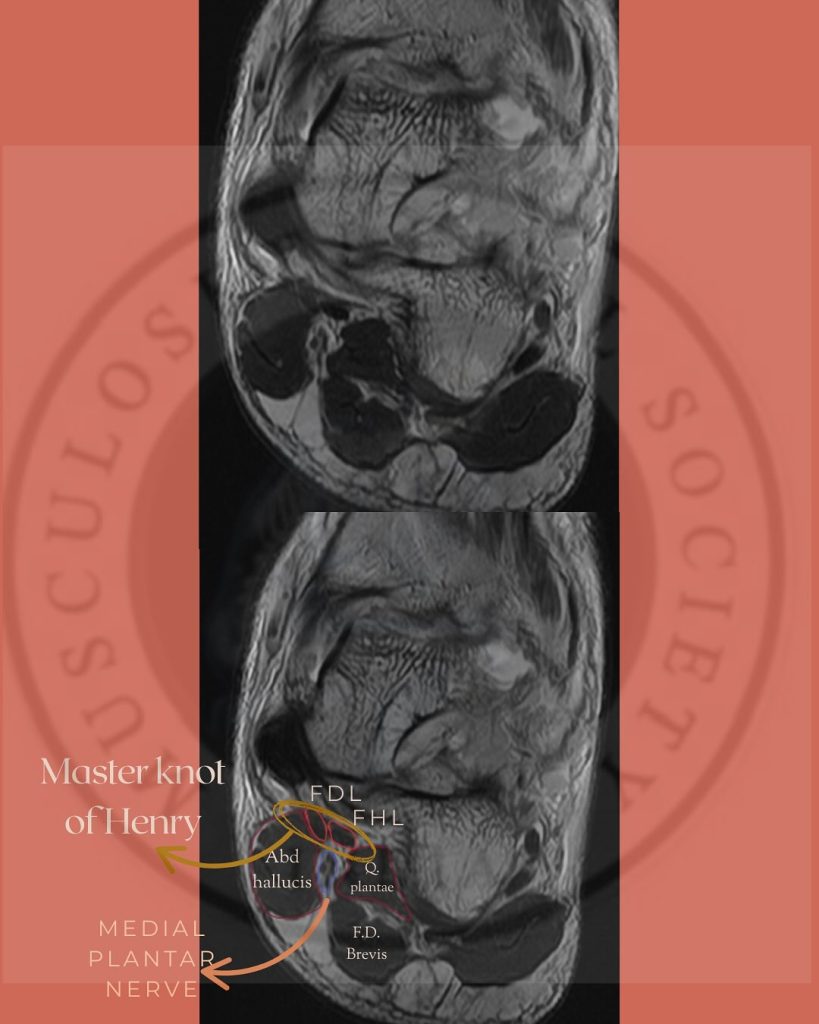

Пальпация медиального подошвенного нерва (MPN)

Анатомическое расположение:

Медиальный подошвенный нерв является ветвью большеберцового нерва и проходит по медиальной части подошвы стопы. Наиболее частой зоной его компрессии является область бугристости ладьевидной кости, где нерв проходит в узком фиброзно-мышечном туннеле между ладьевидной костью и мышцей, отводящей большой палец стопы [18]. В этой зоне нерв уязвим к механическому сдавлению, особенно при повышенной пронации стопы или гипертрофии мягких тканей.

Пальпация нижнего пяточного нерва (ICN)

Нижний пяточный нерв (первая ветвь латерального подошвенного нерва) отходит вблизи бифуркации большеберцового нерва и проходит медиально и кпереди от бугристости пяточной кости [21]. Он иннервирует надкостницу пяточной кости, подошвенные связки и ряд внутренних мышц стопы. Компрессия нерва часто возникает в пространстве между фасцией мышцы, отводящей большой палец, и квадратной подошвенной мышцей.